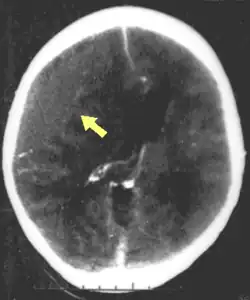

Hematomas, also focal lesions, are collections of blood in or around the brain that can result from hemorrhage.[11] Intracerebral hemorrhage, with bleeding in the brain tissue itself, is an intra-axial lesion. Extra-axial lesions include epidural hematoma, subdural hematoma, subarachnoid hemorrhage, and intraventricular hemorrhage.[38] Epidural hematoma involves bleeding into the area between the skull and the dura mater, the outermost of the three membranes surrounding the brain.[11] In subdural hematoma, bleeding occurs between the dura and the arachnoid mater.[23] Subarachnoid hemorrhage involves bleeding into the space between the arachnoid membrane and the pia mater.[23] Intraventricular hemorrhage occurs when there is bleeding in the ventricles.[38]

Neuroimaging is helpful but not flawless in detecting raised ICP.[99] A more accurate way to measure ICP is to place a catheter into a ventricle of the brain,[39] which has the added benefit of allowing cerebrospinal fluid to drain, releasing pressure in the skull.[39] Treatment of raised ICP may be as simple as tilting the person's bed and straightening the head to promote blood flow through the veins of the neck. Sedatives, analgesics and paralytic agents are often used.[51] Propofol and midazolam are equally effective as sedatives.[100]